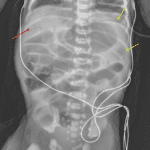

- Extensive portal venous gas

- Mottled and curvilinear lucencies along loops of bowel in the left upper quadrant

- No definite evidence of pneumoperitoneum

- Nonfocal gaseous distension of bowel loops throughout the abdomen

- Enteric tube tip overlies the stomach

- Necrotizing enterocolitis (NEC)

Findings concerning for necrotizing enterocolitis with extensive portal venous gas as well as mottled and curvilinear lucencies along loops of bowel in the left upper quadrant suspicious for pneumatosis.

No definite evidence of pneumoperitoneum. However, recommend left side down decubitus view for a more sensitive evaluation.

Nonfocal gaseous distension of bowel loops throughout the abdomen.

Enteric tube tip overlies the stomach.